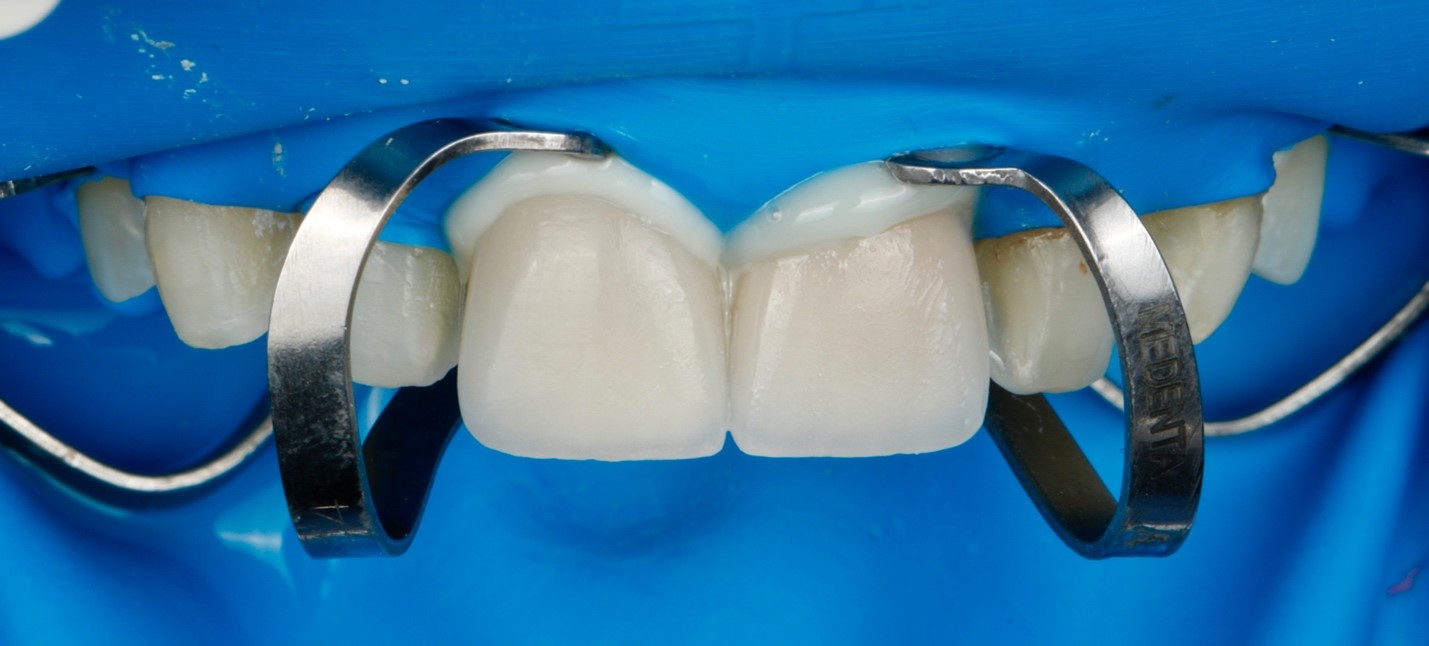

После припасовки виниров в полости рта и определения цементов для фиксации с помощью примерочных паст Variolink Try-In, была проведена изоляция зубов системой коффердам (Рисунок 7). Изначально проведена фиксация колпачка из дисиликата лития на Variolink Esthetic DC Refill (Ivoclar Vivadent AG) оттенка warm (Рисунок 8). Зуб и колпачок были подготовлены в соответствие с протоколом адгезивной фиксации дисиликата лития. Проведен рентгенологический контроль.

Рис. 7. Изоляция зубов коффердамом для адгезивной фиксации.